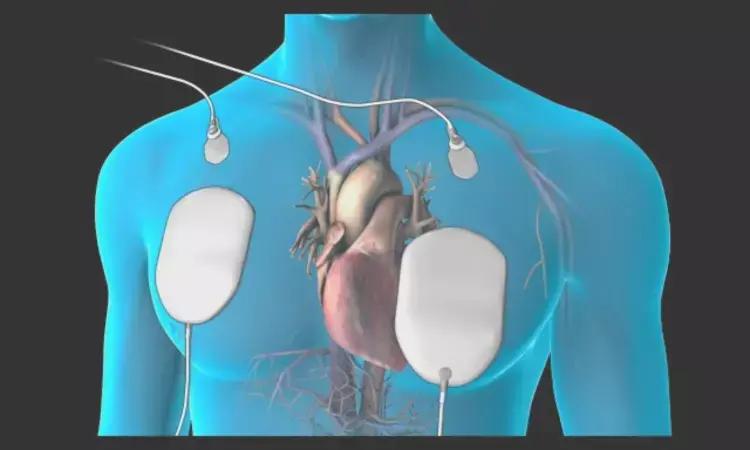

Electrode Position, AP Or AL, May Not Impact Success Rate Of Cardioversion Of AF

- 18 February 2025

- 4 months ago